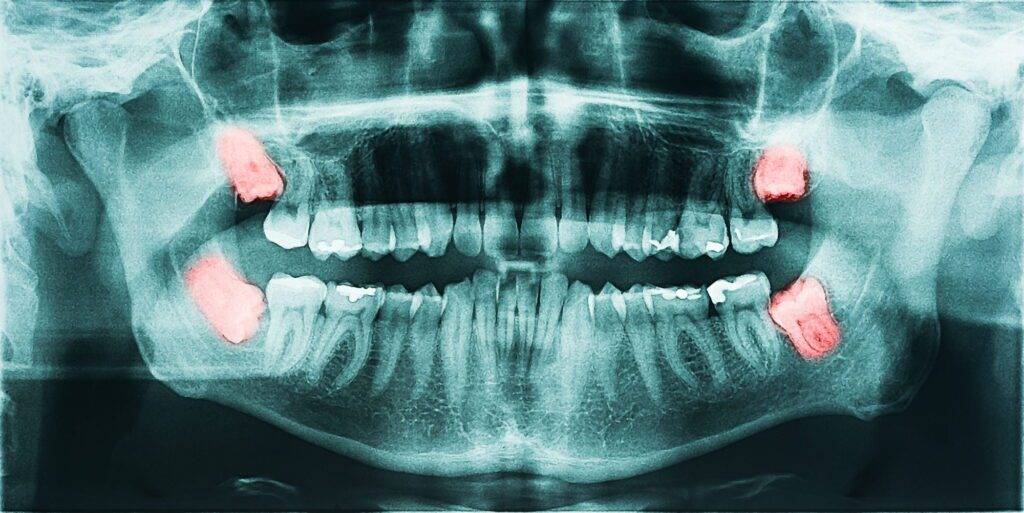

Doktor gigi akan buat X-ray untuk menilai kedudukan gigi bongsu sebelum mencadangkan rawatan.

Keadaan ini boleh menyebabkan gigi bongsu tersepit dalam gusi atau tulang, dan inilah yang dipanggil impacted wisdom tooth.

• tumbuh senget

• tumbuh separuh sahaja

• atau tidak cukup ruang untuk keluar sepenuhnya